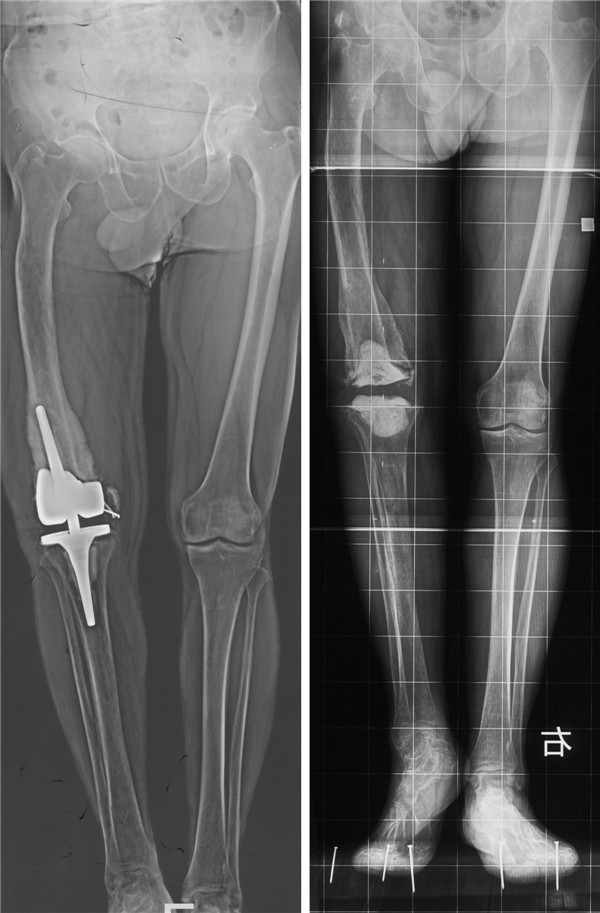

术前X线片

患者男性, 64岁,来我院就诊前已经在外院接受两次膝关节置换,两次假体取出手术,患肢短缩7cm,股骨远端两髁全部吸收,股骨髁上骨干大量纤维骨痂包裹。患者极为痛苦,生活质量极低。另外,很重要的一点,患者经拍股骨全长X光片时发现,左侧股骨中上段内翻畸形。就此病例即使使用普通的定制铰链膝,也无法做到在正确放置假体的同时恢复正常下肢力线和长度。

术后X线片